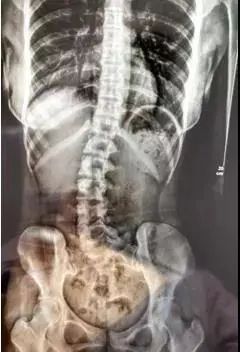

广州一名18岁女孩小邹常出现腰痛、脖子酸等症状。到医院就诊时,医生发现,她的腰椎向右侧弯、旋转,脊柱也向右发生明显侧弯。

原来小邹睡觉时,总是朝着同一个方向侧睡,再加上小邹喜欢斜趴着睡,单腿弯曲,呈“卩”字形。

长期的固定单方向睡姿,使得小邹的脊柱体态逐渐失衡,骨盆发生旋移、腰椎出现旋转,最终导致小邹出现脊柱侧弯,这也是引起她腰酸、颈发酸的主要原因。